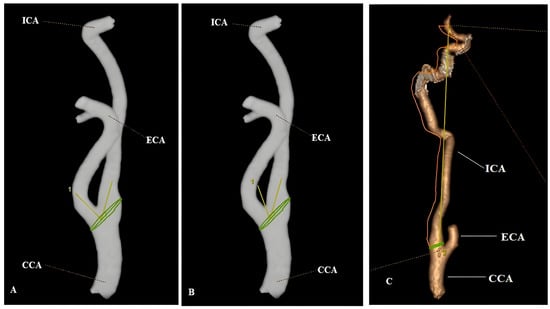

Relationship Between Carotid Artery Anatomy and Geometry and White Matter Hyperintensities and Accompanying Comorbid Factors

Background/Objectives: This study aimed to investigate the relationship between carotid artery anatomy and geometry and white matter hyperintensities (WMH) and to determine whether it is a risk factor for the disease. Methods: The geometry and anatomy of both carotid arteries were evaluated with the three-dimensional vessel model obtained from the computed tomography angiography (CTA) data, and the segmentation software calculated the geometrical features of the arteries. In this model, vascular diameter, vascular cross-sectional area, carotid bifurcation and internal carotid artery (ICA) angles, as well as ICA tortuosity index (TI) measurements of the common carotid artery (CCA) and ICA were determined. Results: Compared with the non-WMH group, increased carotid bifurcation and ICA angle and higher ICA TI values were found in the WMH group (p < 0.001). In multivariate regression analysis, increased carotid bifurcation angle, higher ICA TI values, age, hypertension, and stroke history were identified as independent risk factors for the development of WMH (p < 0.05). In addition, age, carotid bifurcation angles and ICA angles were found to be associated with the severity of WMH (p < 0.05). Conclusions: Considering the vascular pathologies involved in the pathogenesis of WMH, identifying these risk factors may help determine individuals who are at an increased risk. Full article

Figure 1